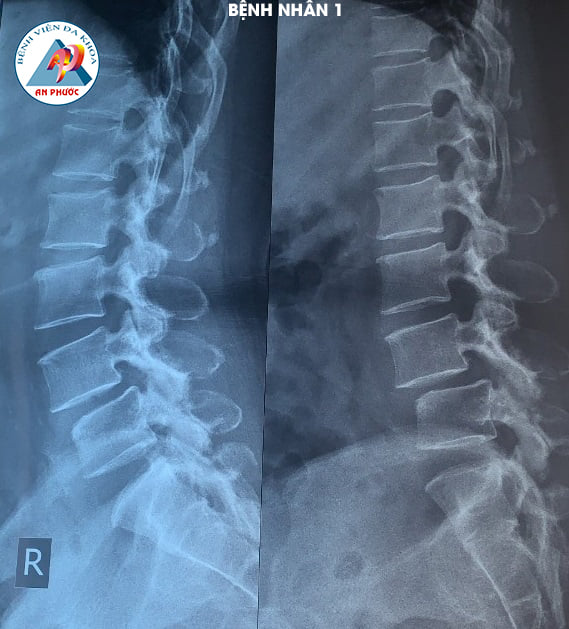

Trường hợp 1: Bệnh nhân nữ, 58 tuổi, ngụ tại Hàm Thuận Nam, Bình Thuận. Vào viện trong tình trạng đau lưng, tê, yếu hai chân hơn 10 năm. Bệnh nhân đã được điều trị nội khoa, kết hợp với tập vật lý trị liệu nhiều lần, ở nhiều Bệnh viện khác nhau, nhưng bệnh không giảm.

Sau khi được Bác sĩ chuyên khoa khám lâm sàng và cận lâm sàng (chụp MRI, XQ CSTL (có Film). Bệnh nhân được chỉ định phẫu thuật: Lấy nhân đệm và làm cứng CSTL bằng nẹp vis, thay đĩa đệm nhân tạo.